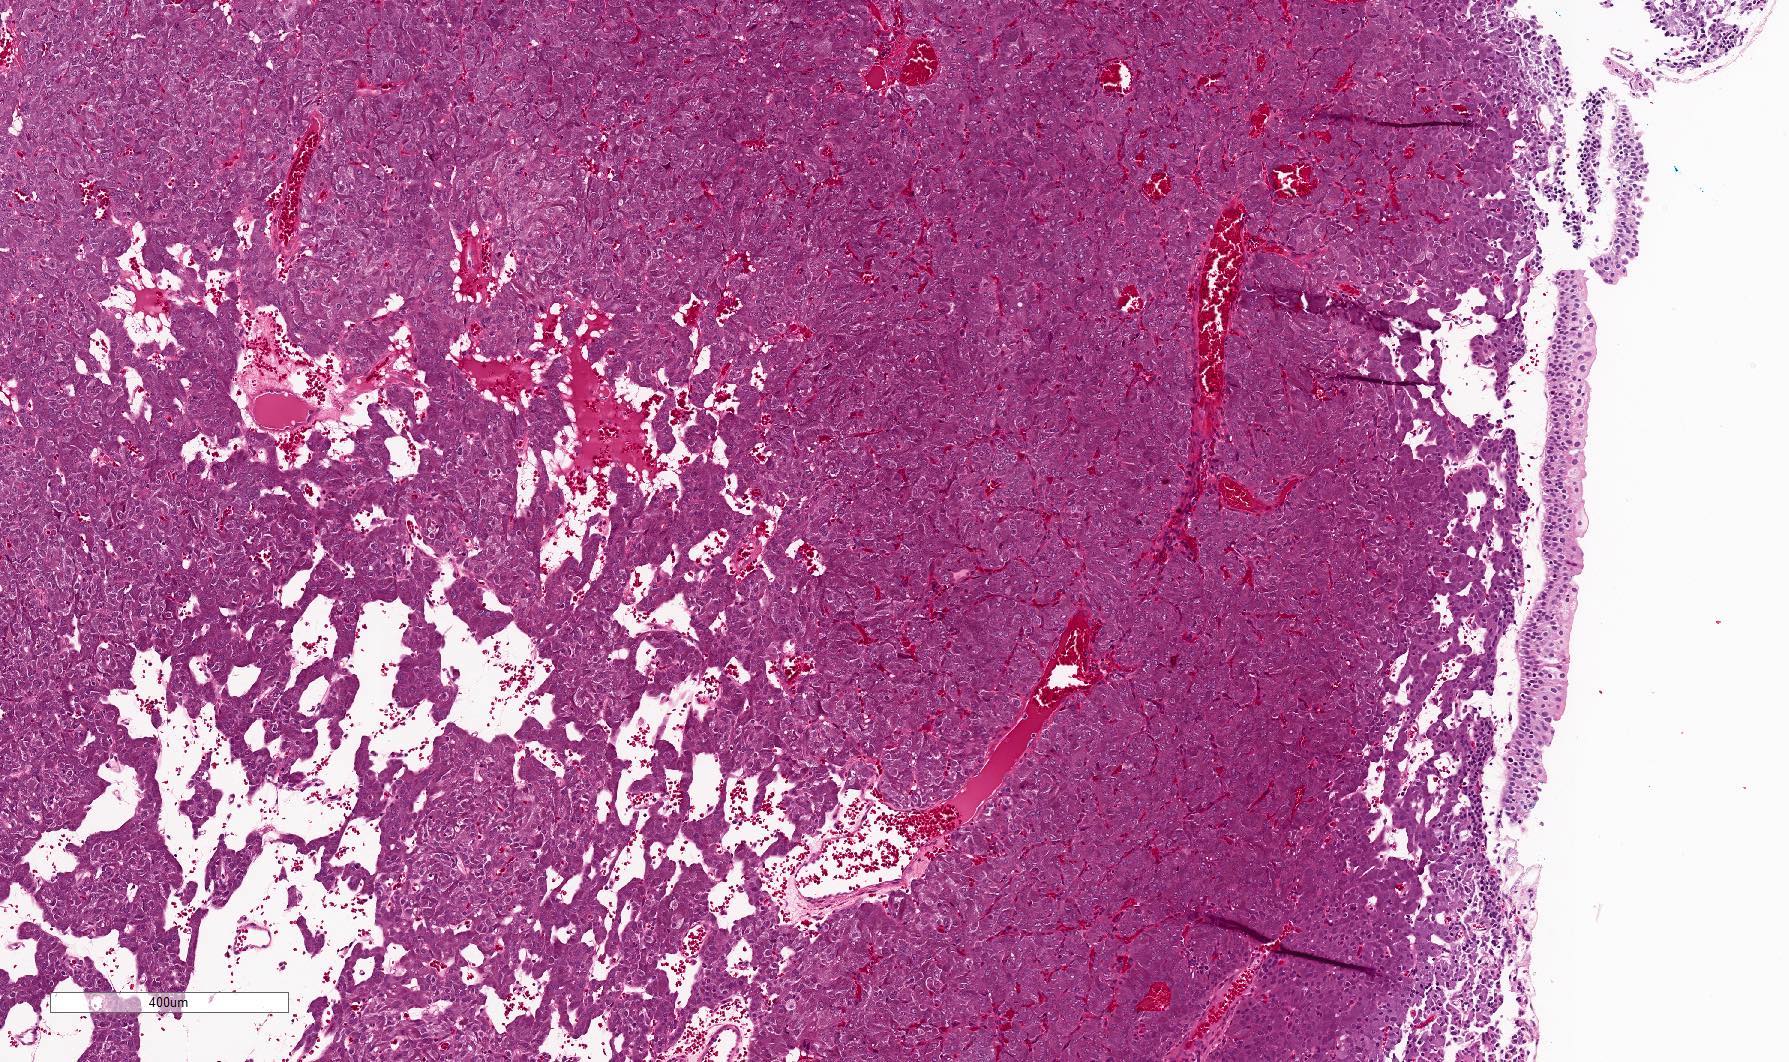

Microscopic (histologic) description

- Typical morphology: epithelioid cells with abundant, eosinophilic / amphophilic, granular cytoplasm and round / ovoid, vesicular / salt and pepper nuclei, arranged in a nested / zellballen pattern and separated by fibrovascular septae with sustentacular cells (Am J Surg Pathol 2004;28:94, World J Clin Cases 2014;2:591, Endocr Pathol 2022;33:90)

- May have focal pleomorphism, nuclear hyperchromasia, low mitotic activity or clear cytoplasm

Microscopic (histologic) images

Contributed by Theodorus H. van der Kwast, M.D., Ph.D., Michelle R. Downes, M.D., Debra L. Zynger, M.D. and David Cohen, M.B.B.Ch., M.D.

- Microscopic description: This specimen shows an unencapsulated, monomorphous population of round tumor cells in a nested / zellballen pattern with delicate vascular septa and intervening extravasated red blood cells. It predominantly involves the lamina propria of the bladder but in 1 tissue piece clearly involves muscularis propria. The tumor cells have abundant amphophilic cytoplasm and vesicular chromatin with occasional small nucleoli. There is no necrosis, diffuse growth pattern or vascular space invasion identified. The mitotic count is (maximally) 1/10 high power fields. Immunohistochemistry shows the tumor cells to be positive for GATA3 with strong and diffuse expression of synaptophysin and chromogranin, as well as retention of SDHB staining. The tumor cells are negative for AE1 / AE3, HMWK and p63. The Ki67 proliferation index is < 1%. S100 shows faint nuclear and cytoplasmic staining with occasional sustentacular cells identified.

- Microscopic description: Sections show unremarkable surface urothelium with a lesion in the deep lamina propria comprised of large eosinophilic cells with hyperchromatic, focally enlarged nuclei with occasional intranuclear inclusions. A fine vascular plexus is identified in some areas. Necrosis and hemorrhage are not identified. Mitotic rate = 1/10 high power fields (field of view [FOV] = 0.55 mm). The lesion extends to the cauterized base of the specimen. Immunostains confirm the lesion expresses synaptophysin, chromogranin and GATA3. SDHB is retained. AE1 / AE3, CD45, p63 and NKX3.1 are negative.